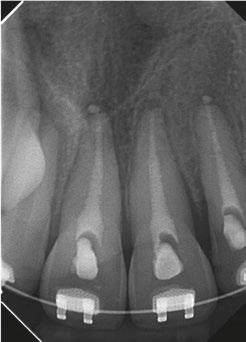

One of the most critical steps in treating dental trauma is making sure you don’t rush things. That means that obturation is often postponed until the patient is asymptomatic (i.e., no pain to percussion) and the periodontal ligament has radiographically re-established itself. Clinicians must also make sure the tooth is completely disinfected of bacteria. Both of these steps are achieved by placing calcium hydroxide as an intracanal medicament during the treatment as seen in Figure 4.

Calcium hydroxide has been shown to be extremely beneficial in the long-term retention of teeth after they have experienced trauma. It can arrest and even repair inflammatory resorption and eliminate harmful bacteria from the root canal system after trauma. Its antimicrobial properties come from its alkaline pH and its ability to dissolve necrotic tissue, bacteria, and their byproducts.1

My personal favorite calcium hydroxide product to use in these delicate clinical situations is UltraCal™ XS paste by Ultradent. It is syringeable, making it very simple to use, since there is no mixing involved. The syringe tip is thin and comes with a rubber stopper that allows placement of the material to be safe and contained within the canal.

Figure 3

Figure 4